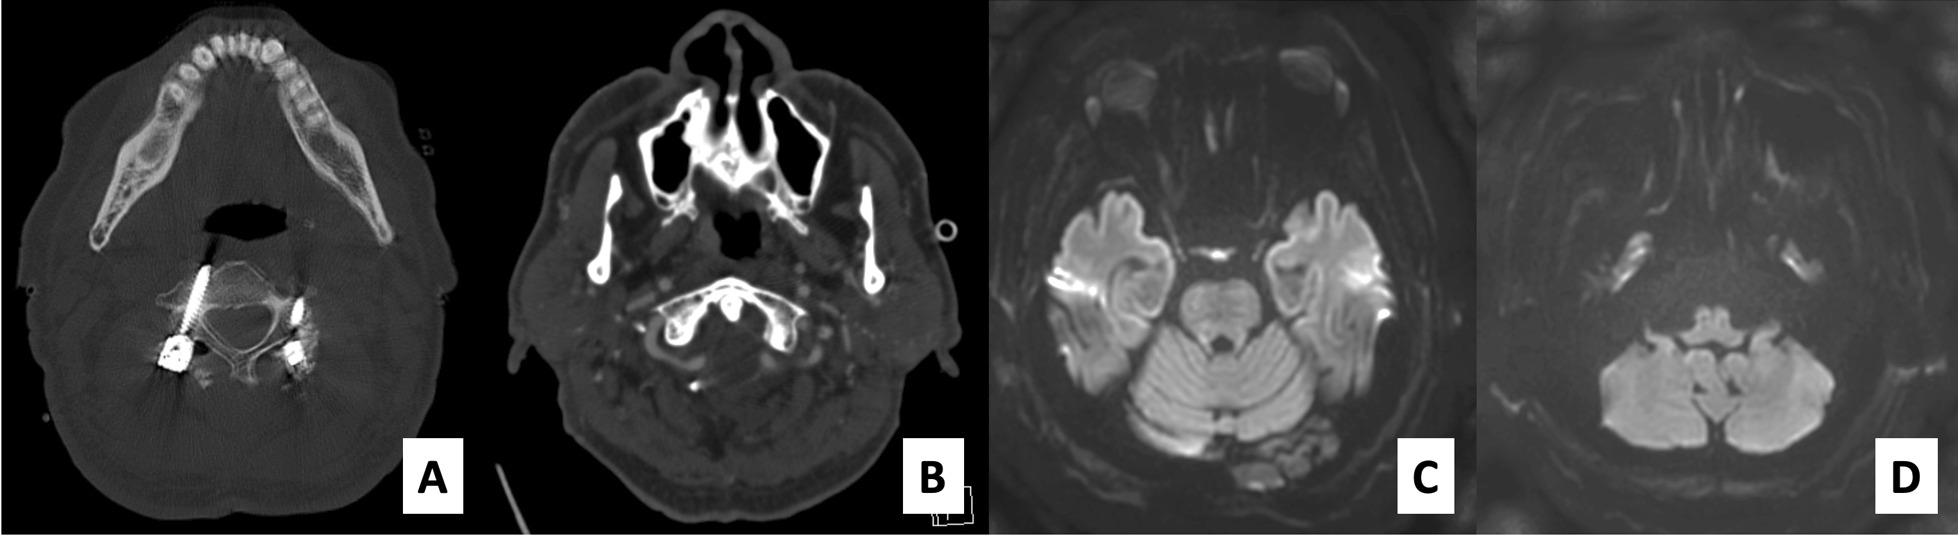

Fig. 2.

Computer tomography reveals the right C3 pedicular screw trajectory, which involves the medial border of the right foramen transversarium and left C3 lateral mass screw (a). Postoperative computed tomography angiography demonstrated a patent of right vertebral artery and good distal flow (b). Postoperative brain magnetic resonance imaging with diffusion-weighted imaging technique did not show any diffusion restriction (c, d)

Fig. 3.

Plain radiographs after the first operation reveal the neutral alignment of the upper cervical spine region. The occiput-C2 angle is − 1.8° (a), the C1–C2 angle is − 25.1° (b) and the craniovertebral junction angle proposed by Takami is 81.1° (c)

Postoperative radiographic examination illustrated that the screw-rod system was intact and that the atlantoaxial alignment was neutral. CT angiography showed no VA injury with good distal flow. MRI of the brain did not demonstrate any evidence of stroke or suspected cause of dysphagia (Fig. 2). Using the McGregor line as a reference of the occipital bone, the occiput-C2 and C1–C2 angles were − 1.8° and − 25.1°, respectively (the minus value indicates that the angle is in lordosis). The craniovertebral angle proposed by Takami et al. [5] to evaluate the craniovertebral fixation angle, namely, the angle between the line parallel to the bony palate and the posterior longitudinal line of vertebrae of C2, was 81.1°. The space between the posterior border of the mandible and the anterior of the cervical spine was narrowed, as was the distance between the screw-rod fixation system and the occiput (Fig. 3). Taken together, these findings led us to believe that the cause of the trismus and dysphagia was the position of the screws. Therefore, an operation to adjust the position of the C1 and C2 screws to be relatively more extended position was performed on the eighth day after the first surgery.